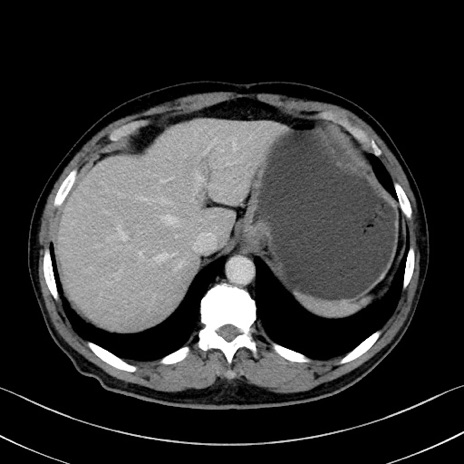

症例35(横断像)

【症例】70歳代 男性

【主訴】腹部膨満、嘔吐

【現病歴】昨日より腹部膨満感出現。本日増悪し、仙痛出現。嘔吐あり、受診。

【既往歴】糖尿病、胆摘後

【身体所見】BP 149/80mmHg、HR 74/min、BT 35.9℃、腹部:膨満、軟、圧痛なし。腸雑音減弱あり。上腹部正中切開瘢痕あり。

【データ】WBC 13500、CRP 1.72